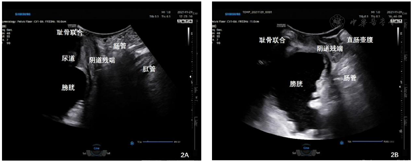

三维盆底超声检查提示:残余尿量160 ml,逼尿肌厚度6.5 mm,膀胱壁上可见小梁样凸起,尿道内口关闭。静息状态:膀胱后角完整,膀胱颈位于耻骨联合水平线上27 mm,阴道残端位于耻骨联合水平线以上37 mm,直肠壶腹部位于耻骨联合水平线以上15 mm;Valsalva动作:膀胱颈移动度49 mm,膀胱位于耻骨联合水平线以下23 mm,膀胱后角开放,尿道旋转角82°,尿道内口漏斗形成,阴道残端位于耻骨联合水平线以下34 mm,可见部分小肠自阴道后方直肠前方脱出于阴道外口,直肠壶腹部位于耻骨联合水平线。未及直肠膨出声像,肛提肌裂孔大小约47 cm2,未见明显肛提肌及肛门括约肌断裂声像(图2)。